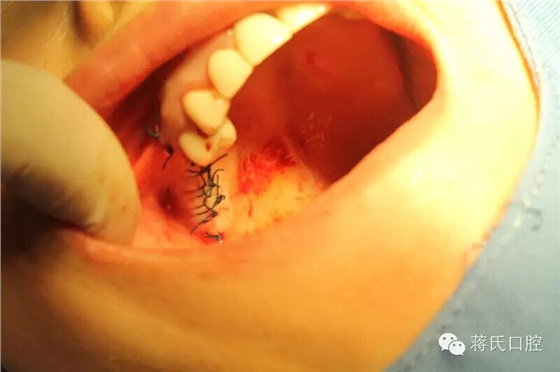

8.右側(cè)縫合后